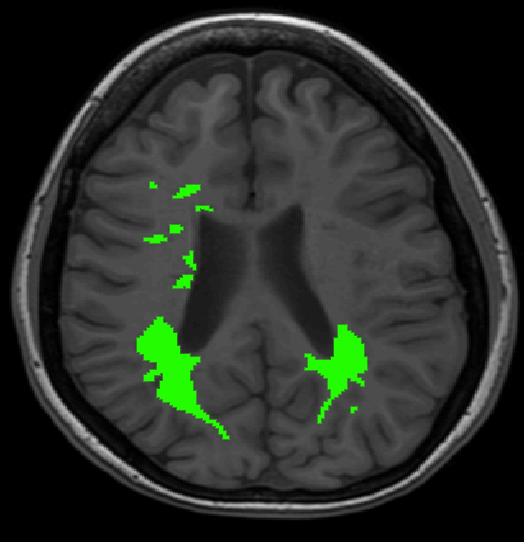

We use images from three different studies (see Fig. 1 for examples of slices):

10 MS patients from the MS Lesion Challenge [11] scanned at the Children’s Hospital of Boston (CHB), scanned with T1, T2 and FLAIR at 0.50.50.5mm resolution.

10 MS patients from the MS Lesion Challenge [11] scanned at the University of North Carolina (UNC), scanned with T1, T2 and FLAIR at 0.50.50.5mm resolution.

- 3.

Here again the differences between study populations influence the class priors. On average, the percentage of voxels that are lesions are 1.6%, 2.6% and 0.2% in CHB, RSS and UNC respectively. The differences between subjects also vary: these are relatively small for CHB and UNC, but very large for RSS. In RSS, the subject with the least lesion voxels has only 0.08%, while the patient with the most lesion voxels has 14.3%.